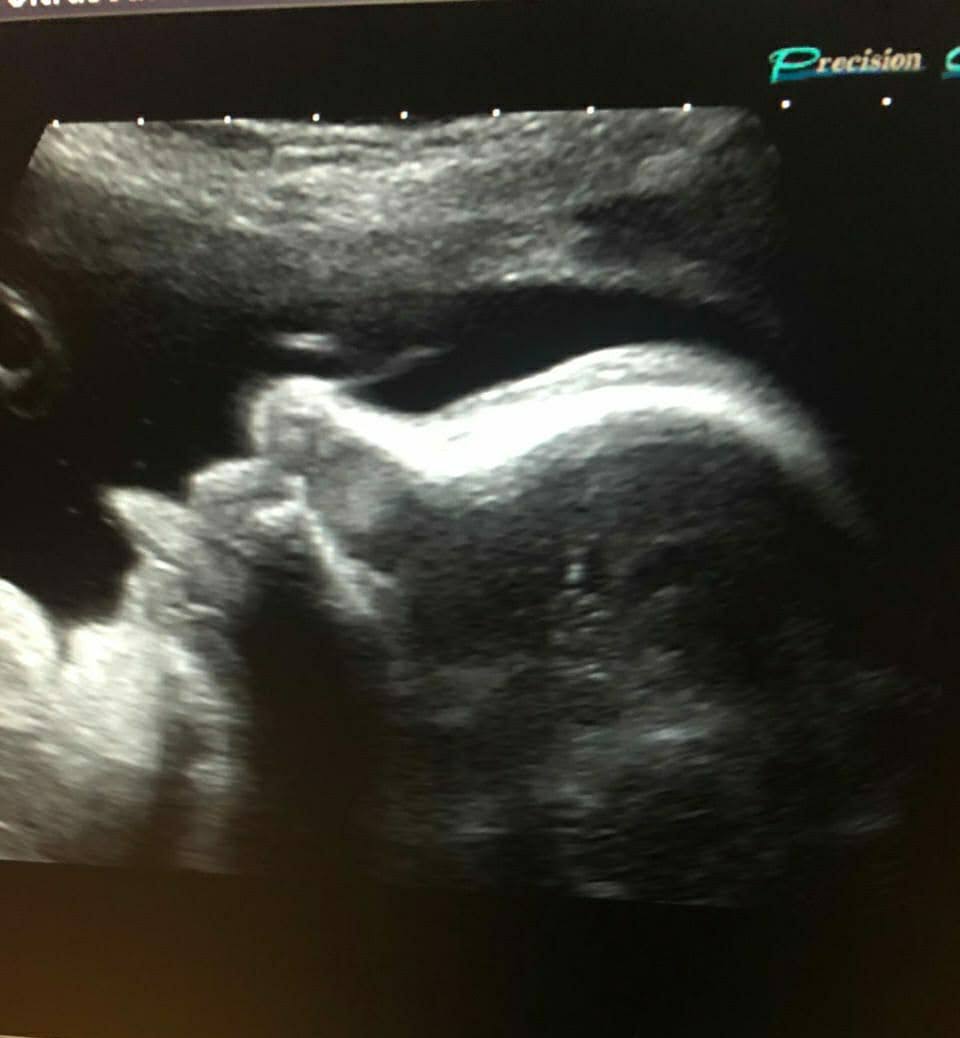

Кожне УЗД дослідження — це можливість побачити унікальні моменти розвитку вашої дитини. Наша мета — не лише провести точну діагностику, але й подарувати вам ці незабутні спогади.

УЗД зображення дитини - унікальні моменти розвитку

Скринінги I–III триместрів вагітності в нашому кабінеті в Дніпрі, розрахунок ризиків хромосомних аномалій, виявлення патологічних станів плода та вад розвитку. Допплерографія плода.